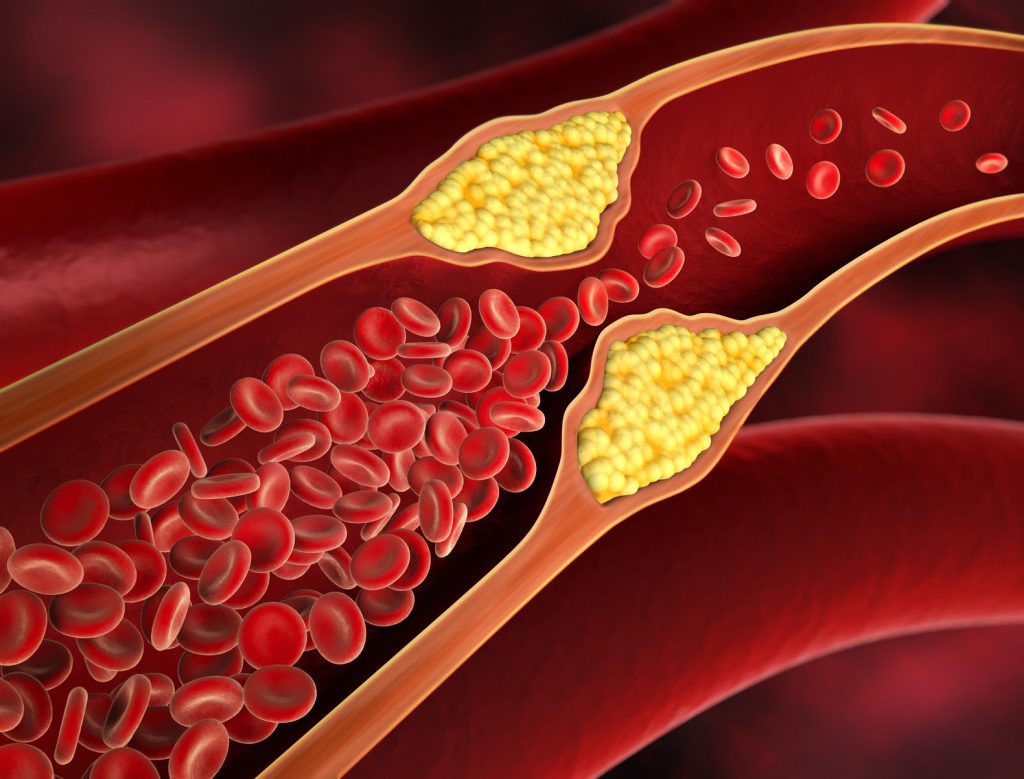

October 30, 2023Izraz bolezni srca in ožilja se nanaša na bolezni krvnih žil in srca. So eden od glavnih vzrokov smrti na svetu. Nekatere pogoste bolezni srca in ožilja so hipertenzija (visok krvni tlak), cerebrovaskularne in periferne žilne bolezni, miokardna ali ishemična žilna bolezen.

Ali so bolezni srca in ožilja nevarne? Da, bolezni srca in ožilja so lahko zelo smrtonosne. Povzročijo lahko smrt zaradi srčnega infarkta, možganske kapi ali srčnega popuščanja. Z zgodnjim odkrivanjem in ustreznim zdravljenjem lahko tveganje močno zmanjšamo.

Vas zanima več informacij o učinkih zdravila Somasnelle Gel? Naravni pripravki so odličen način za izboljšanje vašega splošnega zdravja. Z njimi lahko tudi ohranite svoje zdravje. Somasnelle Gel ima najboljšo učinkovitost pri hipertenziji zaradi svoje sposobnosti varnega zniževanja krvnega tlaka. Prav tako krepi krvne žile. Somasnelle Gel se je izkazal kot učinkovito mazilo za cirkulacijo krvi, ne glede na vašo starost.

- Izboljša se raven holesterola LDL

- Krvne žile brez maščobnih oblog

- Zdrav krvni obtok je normalen pretok krvi

- Preprečevanje srčnega infarkta in možganske kapi